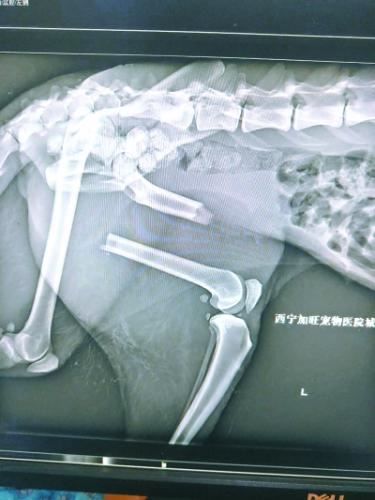

“凌雪”是一只野生老年母雪豹。去年11月末,在经历了车祸、左后腿骨折、被热心牧民发现,并转运到西宁野生动物园后,12月11日,“凌雪”接受了第一次手术,暂时保住了性命。术后,“凌雪”很快恢复活动能力,开始有跳跃行为。43天后,植入的钢钉断裂,钢板变形,第一次手术宣告失败。西宁野生动物园随即通过网络求助,经过多名兽医专家会诊,最后决定运送“凌雪”来京接受第二次手术。

“凌雪”左后腿受伤严重

经过两周的治疗和调养,“凌雪”恢复了自主排便能力,感染也得到明显控制,外伤恢复情况良好,脑震荡症状基本恢复。在体力和精神状态满足复位手术的前提下,12月11日,“凌雪”接受了左后肢股骨复位手术。

“10岁对于雪豹而言,相当于人类的50岁。它受伤后,左后腿腿骨折断,被撞断的左腿磨破了一大片皮,整个下唇从下巴上撕裂下来,上唇右侧被右下犬齿戳了一个洞。”齐园长说,“凌雪”算得上是一只网红雪豹,它的伤情牵动着很多网友的心。西宁动物园方面也通过微博和微信,及时公布“凌雪”的治疗和恢复情况。

今年1月23日,饲养员发现“凌雪”步态异常,似乎又不能用力了。饲养员随即联系兽医,将“凌雪”麻醉后再次拉到动物医院拍片,结果令所有人大吃一惊,同时也心底一凉:“凌雪”左后肢股骨的加固钢钉折断了3根,钢板扭曲,股骨再次移位,它的腿又断了!